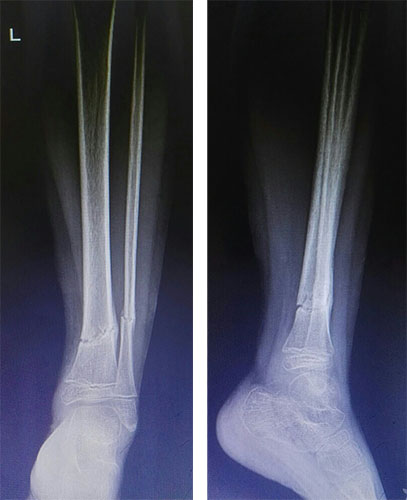

4个月后复查: